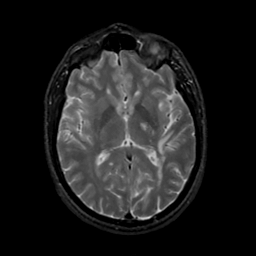

MR Study #20 October 6, 1991 -- Slice #26